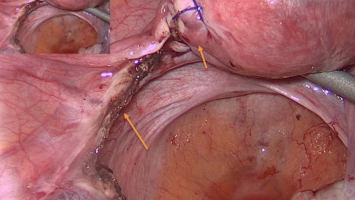

Medizinisches Rätsel: HCG-Wert erhöht trotz fehlendem intrauterinen Befund?

Eine 36-jährige Drittgravida stellt sich mit erhöhten β-HCG-Werten vor, obwohl sonographisch keine intrauterine Schwangerschaft nachweisbar ist. Voraus gingen eine Tubargravidität mit Salpingektomie links, eine Frühgeburt bei 35+5 SSW infolge vorzeitigen Blasensprungs sowie eine laparoskopische Appendektomie. Welche Ursache ziehen Sie in Betracht?

e.Med Interdisziplinär Icon, Search Icon, Transvaginaler Ultraschall/© Graphicroyalty / stock.adobe.com (Symbolbild mit Fotomodellen), Glaszellentumor der Gebärmutter/© Boeker M et al. / all rights reserved Springer Medizin Verlag GmbH, Extrauteringravidität /© Tsitlakidis I et al. / all rights reserved Springer Medizin Verlag GmbH, Bilaterale ausgedehnte zylindrische Bronchiektasen/© Düsterhöft D et al. / all rights reserved Springer Medizin Verlag GmbH, CT des Uterus einer 47-Jährigen /© Rizos A et al. | all rights reserved Springer Medizin Verlag GmbH, MRT des Beckens: Uterus und Ovarialtumoren/© Hosten AK et al. / all rights reserved Springer Medizin Verlag GmbH, Digitales Blutdruckmessgerät/© Kotchakorn / Stock.adobe.com (Symbolbild mit Fotomodell), Frau tastet ihre Brust ab/© Pheelings Media / Getty Images / iStock (Symbolbild mit Fotomodell), Feten von siamesischen Zwillingen/© Zahn E et al. / all rights reserved Springer Medizin Verlag GmbH, MRT einer intrakavitären Raumforderung/© Lattermann M et al. doi.org/10.1007/s00761-025-01733-0 unter CC-BY 4.0, Aufnahme nach Resektion der Extrauteringravidität/© Antonia Jörger